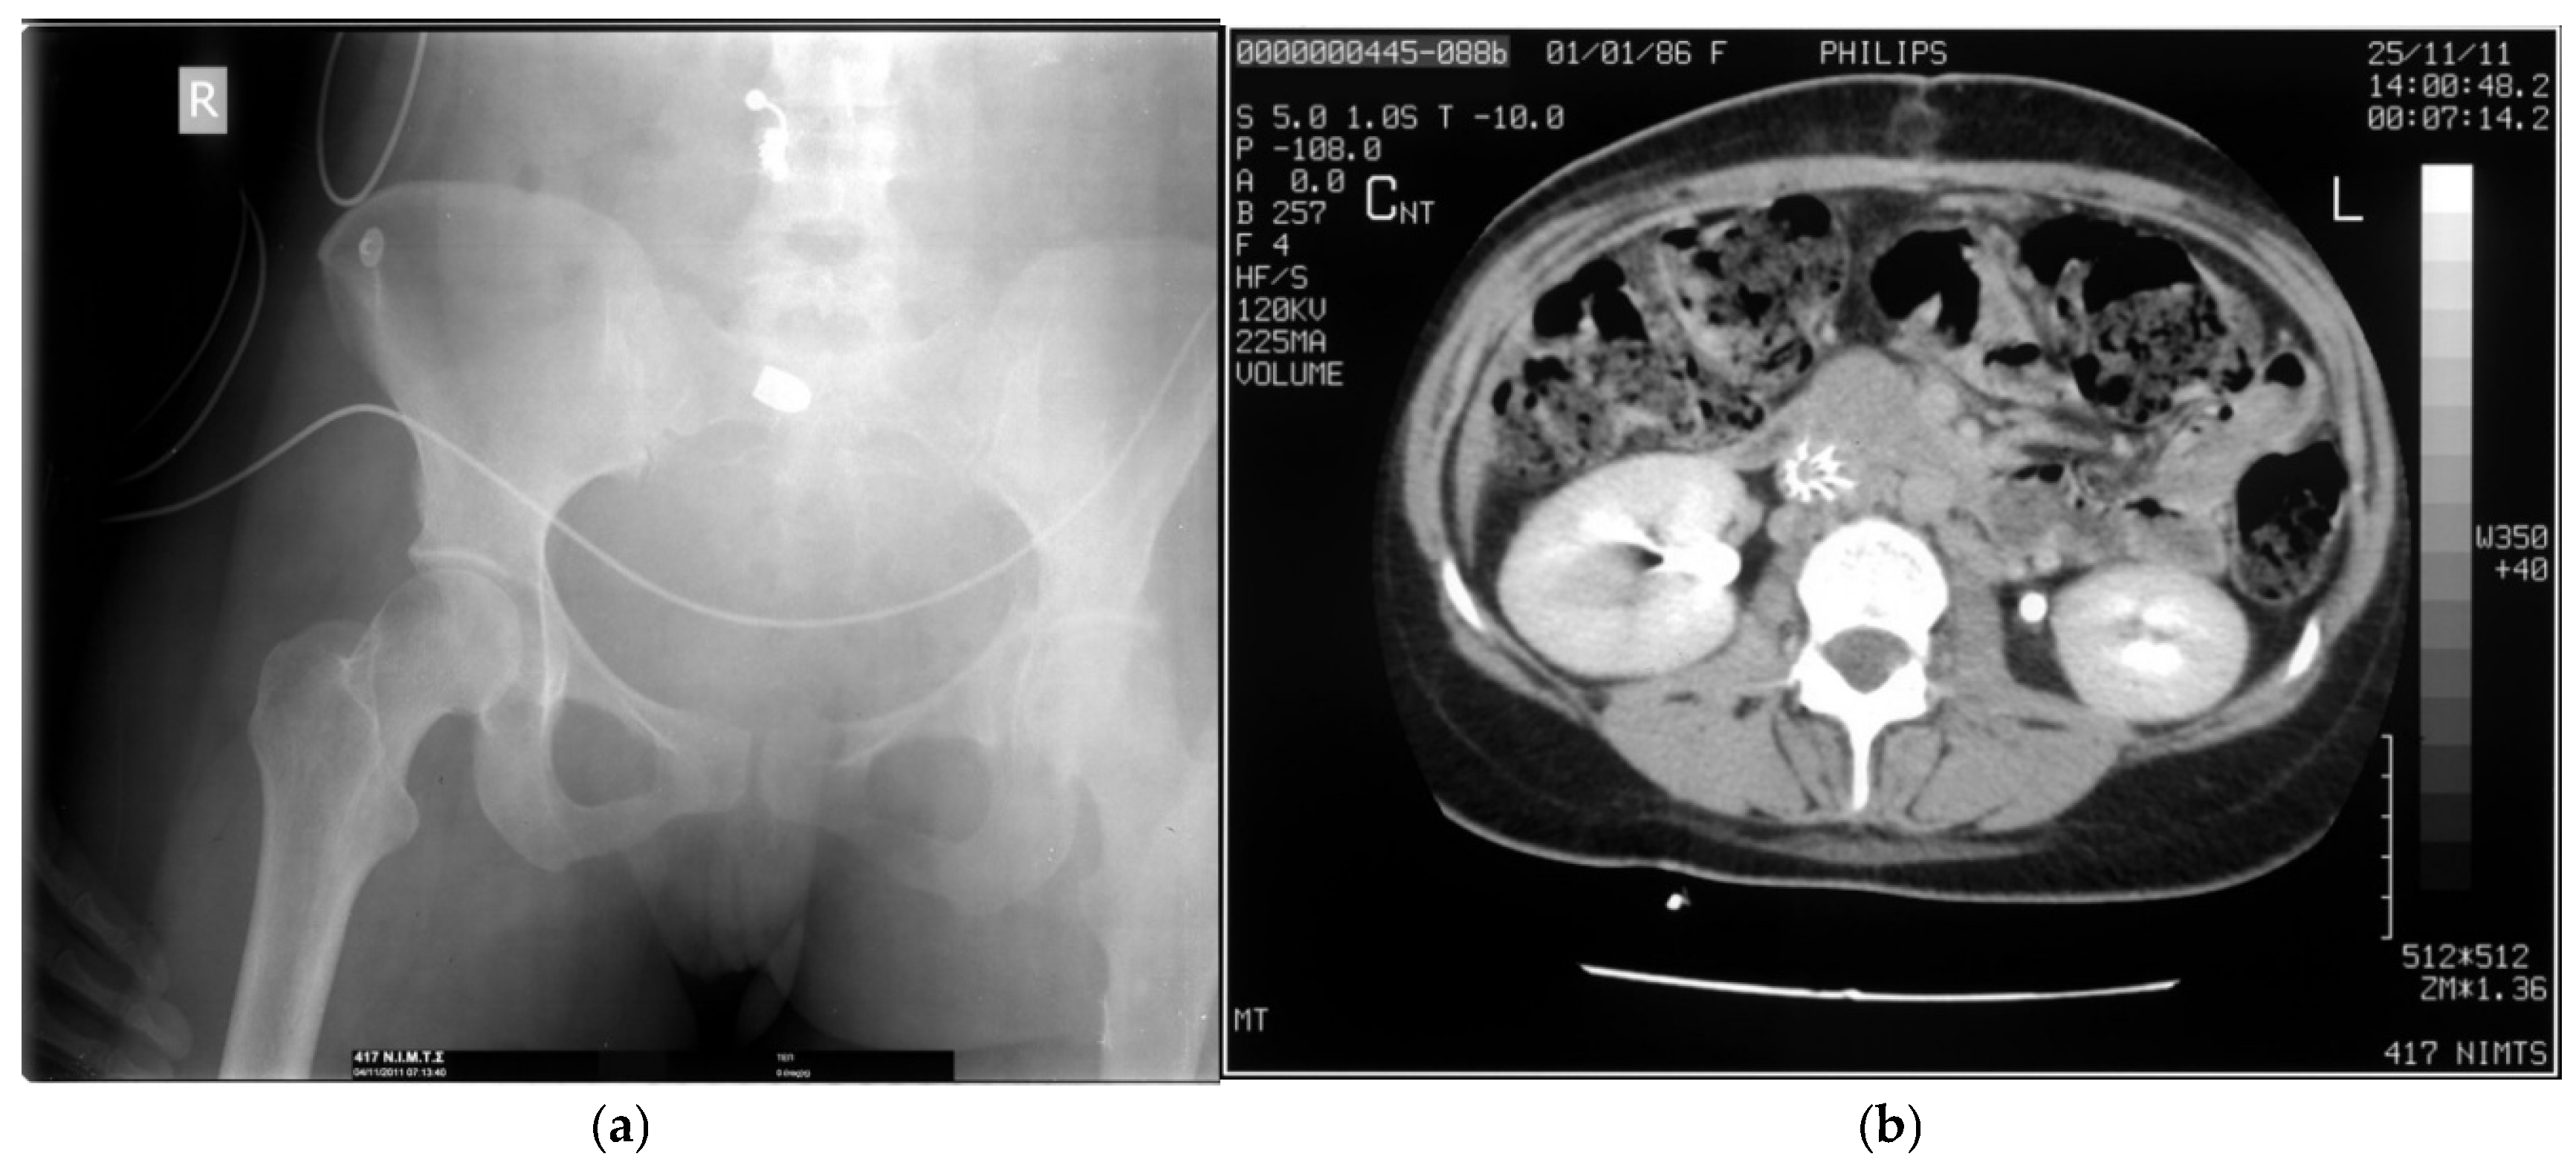

3.2. Trajectory Analysis and Imaging

- Reginelli, A.; Russo, A.; Maresca, D.; Martiniello, C.; Cappabianca, S.; Brunese, L. Imaging assessment of gunshot wounds. Semin Ultrasound CT MR 2015, 36, 57–57. [CrossRef]